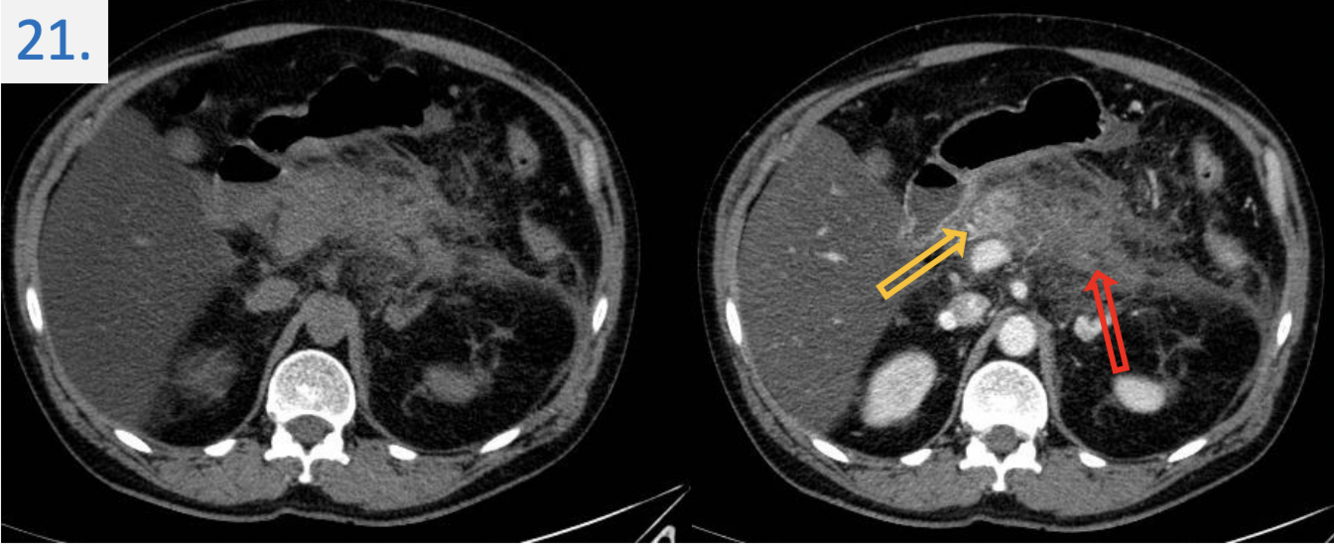

21

Modality:“mDIXON” dynamic contrast-enhanced MR after iv. gadolinium

(noncontrast, arterial phase, portal phase, venous phase)

Region:

upper abdominal MR study (axial view)

Diagnosis:

hepatic focal nodular hyperplasia (FNH)